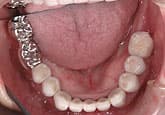

MJさん(20歳・女性)

初診時:左上の歯肉が痛い

初診時

3週間後

さらに正しいはみがき

を行って3週間後

ここまで患者さんが丁寧に歯をみがいただけです。

歯科医と衛生士は何もしていません。

さらに3週間後

歯石除去

歯石が見えてきたので、歯石を除去しました。

健康な歯肉に回復しました。